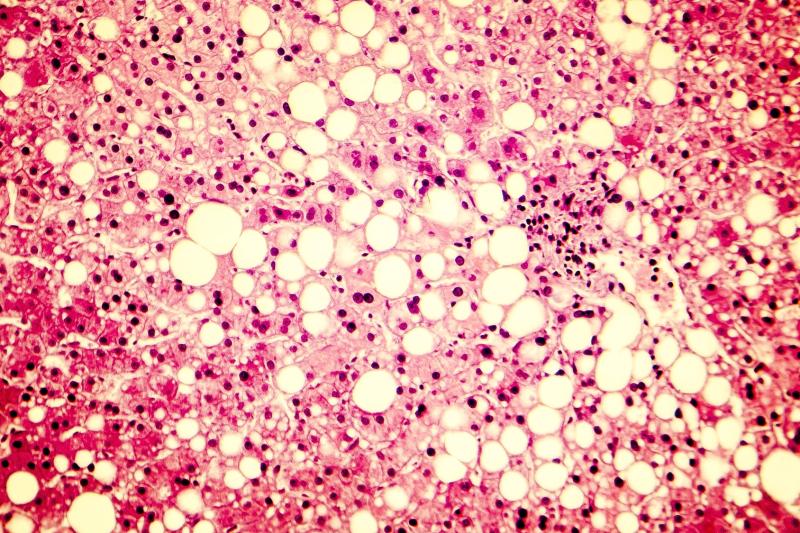

In the treatment of patients with nonalcoholic steatohepatitis (NASH), the glycoPEGylated FGF21 analogue pegozafermin appears to confer beneficial effects on hepatic and metabolic parameters while being well tolerated, according to the results of a phase 1b/2a clinical trial.

Of the patients, 19 completed the study. The primary endpoint of ≥2-point improvement in NAFLD activity score with ≥1-point improvement in ballooning or lobular inflammation and no worsening of fibrosis was documented in 12 patients (63 percent).

Twenty-six percent of patients showed an improvement in fibrosis without worsening of NASH, whereas 32 percent achieved NASH resolution without worsening of fibrosis.